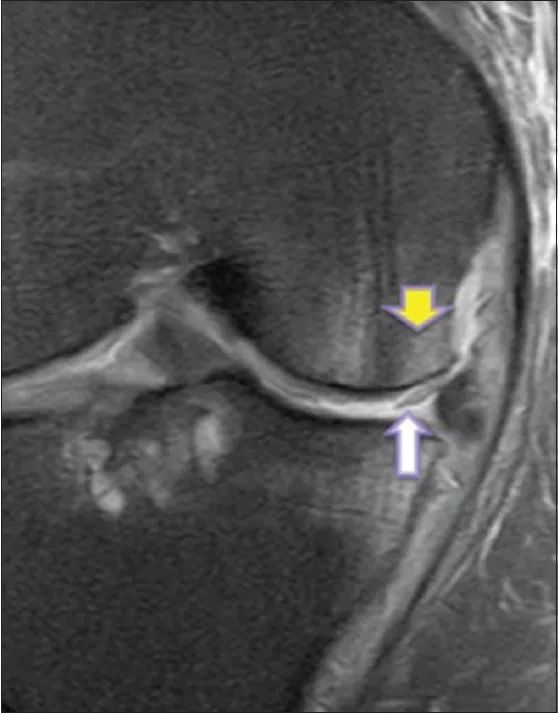

図12 Kellgren Lawrence による膝OA 重症度分類4 MRI を用いた臨床診断もさまざまな定量的な評価方法が報告されている813.先行研究 においては,関節軟骨変性の検出についての報告が多いが半月板を扱っているものもいく12骨挫傷および半月板損傷 膝痛の原因は様々ですが、膝関節内の半月板・軟骨・靱帯などの状態を調べるのに、MRI検査は非常に役立ちます。 この症例では脛骨の骨挫傷(→)と内側半月板後角損傷(*→)を認めます。 MRIトップ | 1乳腺疾患 | 2脳2 膝の固定方法 膝関節mriで最も重要な関節内構成要素のひとつに前十字靱帯(acl)がある。 mri機器に付属する膝用コイルのほとんどは円筒形であるが(図1),通常,円筒 形コイルに膝をセットし固定すると,膝は伸展位になる傾向がある。この場合,

案例教学 膝关节半月板撕裂的mri诊断

半月板损伤的mri分级及检查 骨科基础 3u文域

案例教學 膝關節半月板撕裂的mri診斷 壹讀